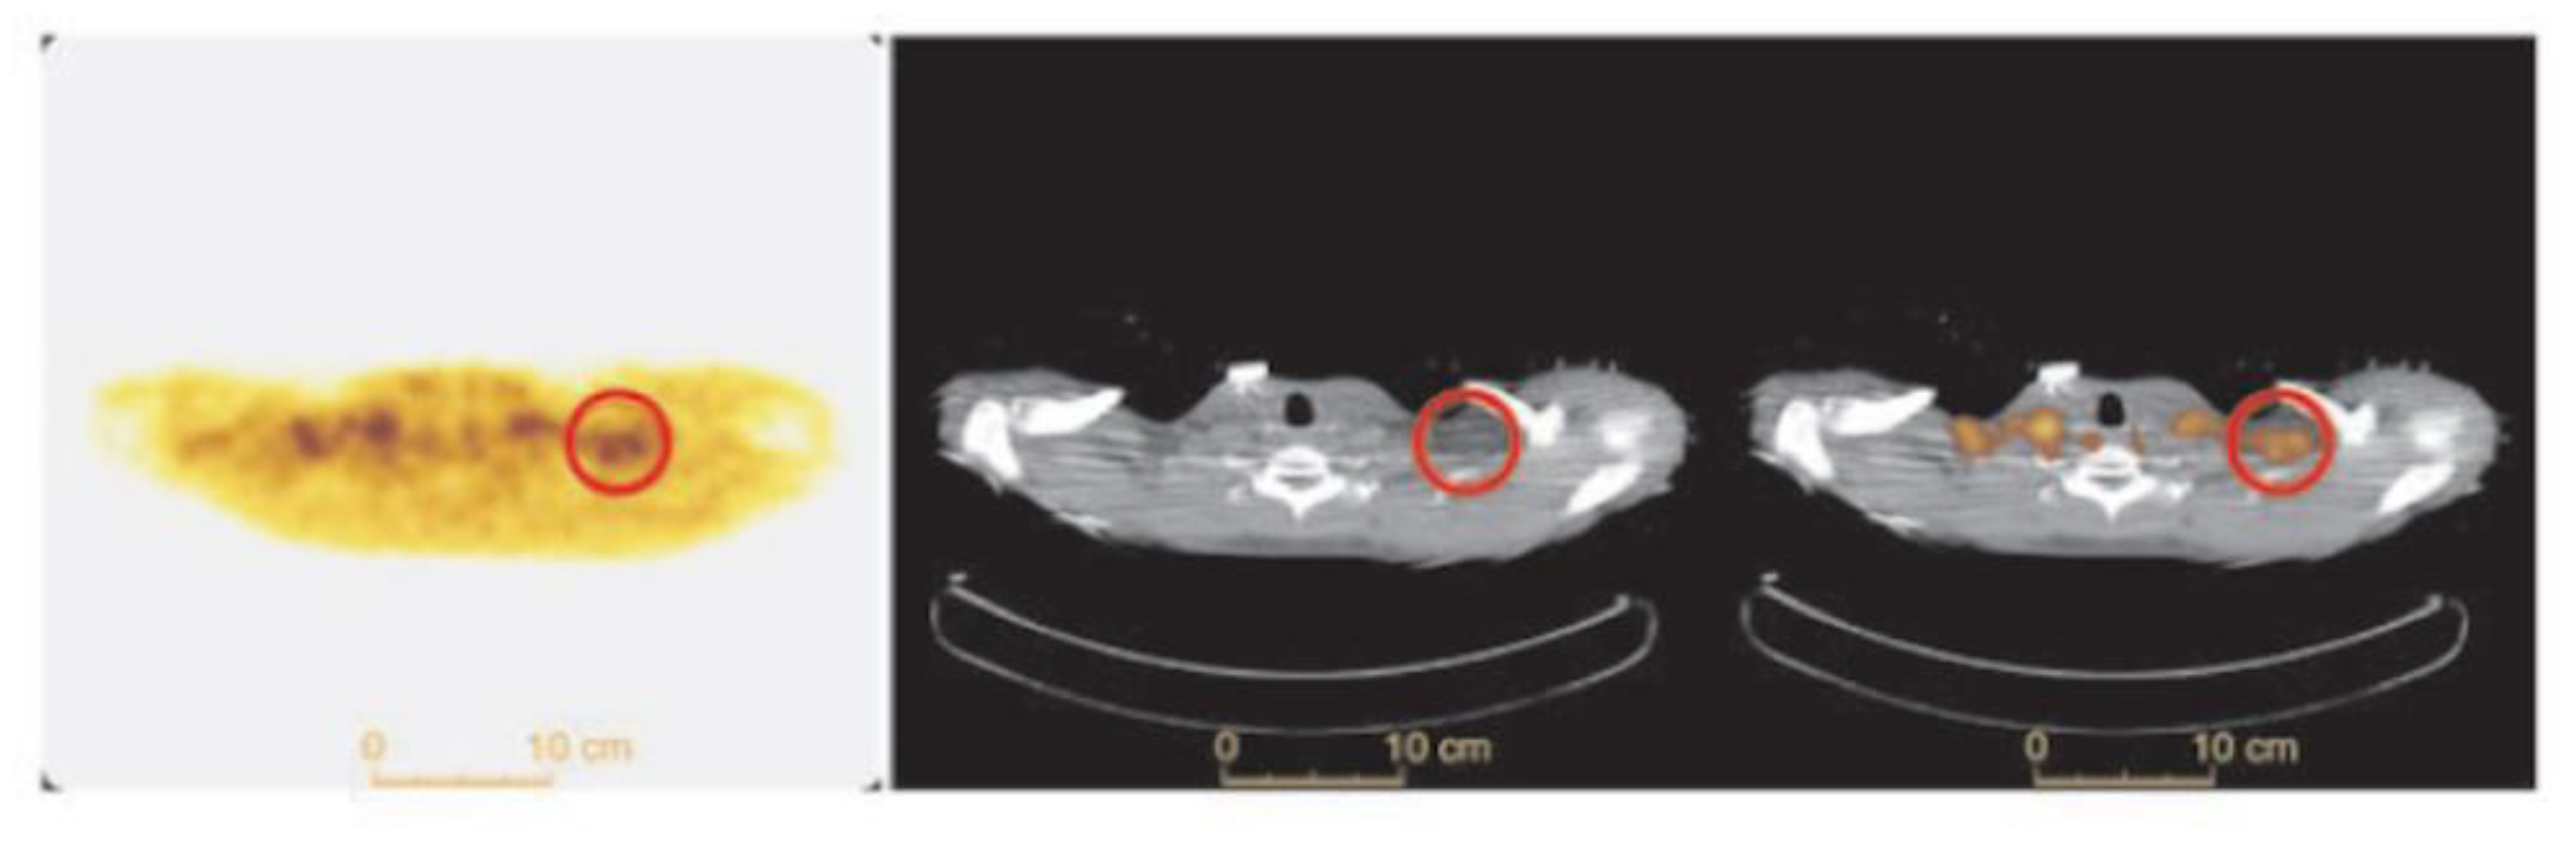

Figure 7.

BAT FTHA uptake in a healthy human subject. Transverse FTHA-PET (left panel), CT (middle panel) and fused PET/CT (right panel) in a healthy subject after 1 h of cold exposure. Supraclavicular BAT is shown in the red circle. Image reproduced with permission from reference 28.